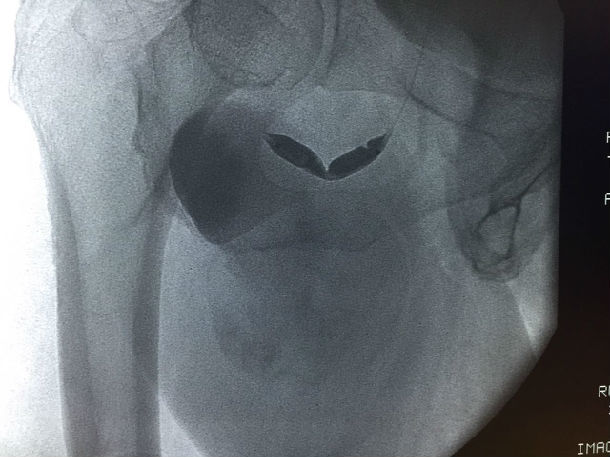

入院后查体:患者右腹股沟下1cm处可见一搏动性包块,6*9cm,边界清楚,质偏软,表面无红肿及淤血,表面皮肤完整,无破溃。

超声提示:右侧腹股沟区见假性动脉瘤形成伴附壁血栓形成,囊性包块6.5*10.3cm,与髂外动脉相同,可见红蓝相间的血流信号。

春节将至,能否给患者和医务人员的我们一个满意的答卷呢?周全的手术方案和万全的准备是必须的。看似简单的股深动脉瘤,确实是对我们技术的严峻挑战。分析病例我们不难发现该病例的一些特点:如果我们采用传统的外科手术方式是较为安全的,但是其中潜在的问题,如开刀风险、手术创面大,术后淋巴管漏等并发症较多,另外术后恢复时间较长,在这特殊时间内对患者来说并不是最好的选择。有没有更简单、经济、创伤较小的方法呢?经讨论后提出多种手术方案:最理想治疗是用小型覆膜支架封堵瘤体口,但是,根据患者下肢血管CTA提示,该患者髂动脉严重迂曲,成角偏小,右侧髂动脉迂曲成直角,入路困难,另覆膜支架顺应性差,植入困难,费用也较大,作为备选方案。如果用传统单纯的弹簧圈治疗,巨大假腔,费用大,疗效不确切,并且有可能会有远期不适,也列入备选方案。还有就是经左侧穿刺,翻山至右侧股深动脉,小球囊封闭瘤体口,经球囊向瘤体内注射凝血酶,待自身形成血栓后,释放球囊,用2枚裸支架覆盖瘤体口,这样既减少创伤,减少费用,同时可防止瘤体内血栓脱落至股深动脉,此手术方案较为理想。那么实际操作中会是怎样的结果,我们无法预知,充足的术前准备显得尤为重要。入路的选择:患者高度肥胖,股动脉穿刺困难(脂肪厚股动脉触摸困难,穿刺要求很高,一旦出问题后果不堪设想)。支架的选择,我们联系多方厂家备用所有可能会用到的支架,介入治疗失败或是操作受限后外科的手术也全部就位。2016-02-03手术在计划中进行,患者体型肥胖,股动脉触摸困难,穿刺就是一个挑战,凭我们丰富的经验,一针见血,穿刺成功通过,更严峻的挑战还在后面,置管造影显示,患者髂动脉严重迂曲,多处迂曲近直角,所有的操作都需谨慎小心,防止导管打折、断裂,引起出血,另多次在各个分支和假腔血管间选择,假腔内操作容易导致瘤体破裂,造成大出血,技术难度大。手术紧张而有序,反复确认瘤体开口口径及有无流出道后,球囊顺利送达瘤体口内,经球囊注射凝血酶,能否形成血栓,大家拭目以待。20min过去了,透视见瘤体内预先残留的造影剂不再消失,自身血栓形成,看到了成功的希望,由于患者动脉迂曲严重,翻山鞘管规格有限,覆膜支架顺应性差,鞘管支撑力不够,经各位医生讨论后,决定用2枚裸支架代替,精确定位后,顺利释放支架,复造影见支架位置良好,贴壁良好,无明显血流渗入瘤体,瘤体搏动消失。患者目前恢复良好,预计可以在春节前2天回家过年。